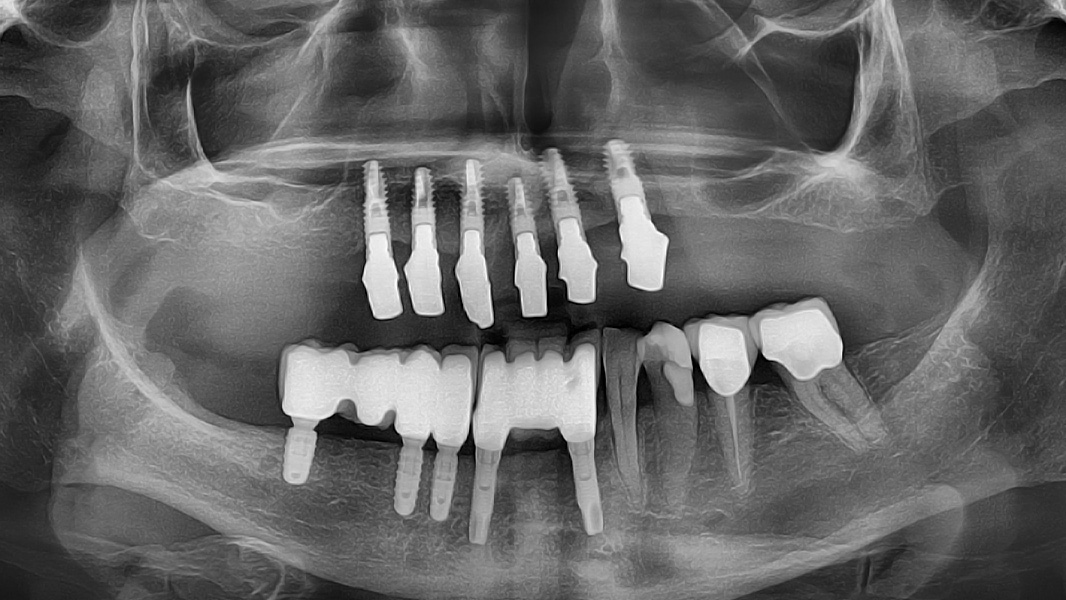

Nicht nur die korrekte dreidimensionale Positionierung der Implantate, sondern auch das Know-how der Knochenaugmentation und die entsprechende Manipulation des Weichgewebes sind essenziell für den Erfolg. Die Kieferknochenrekonstruktion mit autologen Knochenblöcken, die nach der Beschreibung von Prof. Dr. F. Khoury ausgedünnt werden, sowie das Auffüllen der entstandenen Hohlräume mit autologen Knochenspänen führen zu einem vorhersagbaren, langzeitstabilen laminären Knochen. Auch das Implantatdesign mit der parallelwandigen Schulter sowie das Platform-Switching tragen maßgeblich zur erfolgreichen Rekonstruktion bei. Ein weiterer Vorteil des iSy Implantatkonzepts ist die Implantatbasis. Bei transgingivaler Einheilung verbleibt sie bis zur endgültigen Versorgung auf dem Implantat. Die Manipulation des Weichgewebes durch häufigen Abutmentwechsel hat laut Studien einen beachtlichen Anteil an Knochen- und Weichgewebsveränderungen. Auch bei gedeckter Einheilung werden ab dem Zeitpunkt der Freilegung mithilfe der Implantatbasis Abutmentwechsel minimiert.

Ein teilweiser Zahnverlust im Seitenzahnbereich kann zu erheblichen funktionellen Defiziten führen, insbesondere bei jungen Patienten kann er auch ästhetische Probleme verursachen. Störungen des Kiefergelenks (TMJ) treten vor allem dann auf, wenn der Verlust der vertikalen Dimension und die Zahnwanderung nicht frühzeitig behandelt werden. Die Pneumatisierung der Kieferhöhle und der vertikale Knochenabbau im Seitenzahnbereich werden hauptsächlich durch eine nicht behandelte partielle Zahnfehlstellung im Seitenzahnbereich verursacht. In Fällen, in denen die Menge an krestalem Restknochen sehr gering ist, kann die Möglichkeit, den nativen krestalen Knochen auch nach der Knochenregeneration zu erhalten, entscheidend für die langfristige Stabilität der Implantatbefestigung sein. Unter anderem können die Implantatgeometrie und die prothetische Verbindung die Möglichkeit einer krestalen Knochenresorption im Laufe der Zeit beeinflussen. Unter diesem Aspekt bieten die iSy Implantate dank der Geometrie des nicht konisch zulaufenden Implantathalses und der konischen prothetischen Verbindung verbesserte Eigenschaften, die einen langfristigen Erhalt des marginalen Knochens ermöglichen.